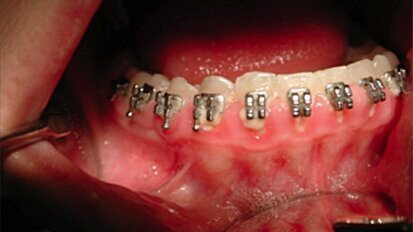

La salute orale dei pazienti ortodontici potrebbe essere migliorata grazie ai batteri probiotici

SONGKHLA, Tailandia – Un nuovo studio ha fornito evidenze supplementari sui benefici dei batteri probiotici contro un gran numero di disturbi orali. ...